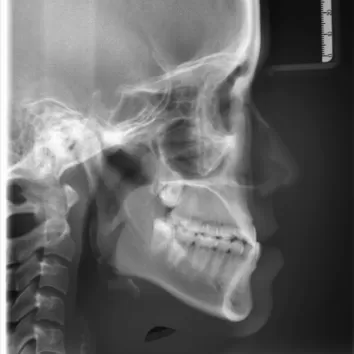

X-rays before treatment

[Panoramic Radiography/Lateral Cephalogram]